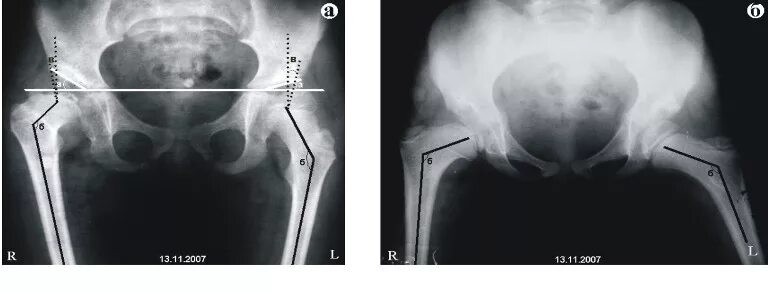

Дисплазия тазобедренного сустава мкб 10